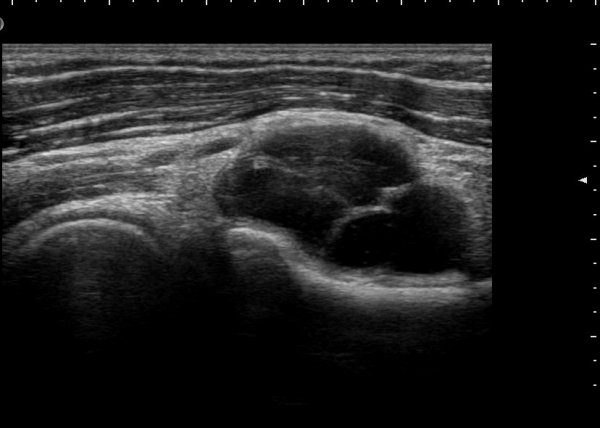

Á¾´Ü¸é°Ë»ç¿¡¼­ Àú¿¡ÄÚ ³¶Á¾ÀÇ Ç¥Ãþ¿¡¼­ Èİñ°£½Å°æºÐÁö°¡ ÀüÀ§µÇ¾î °üÂûµÈ´Ù(±×¸² 4, 5, 6).